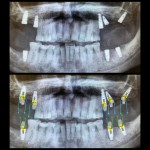

"Il vantaggio di applicare un full arch correttamente in tutti i suoi aspetti si rivela nell'applicarlo senza ritocchi a un paziente al quale è terminato l'effetto dell'anestesia. E' in quel momento che un sistema d'impronta valido come il SOL mostra differenza rispetto ad altri. Se poi questo sistema è comodo per improntare, tanto di guadagnato. Inoltre se il mio paziente manifestasse ipersensibilità nei confronti dei materiali per impronta, gli libero la bocca in tre secondi e riduco il cucchiaio". Dott. Ezio Zandanel -